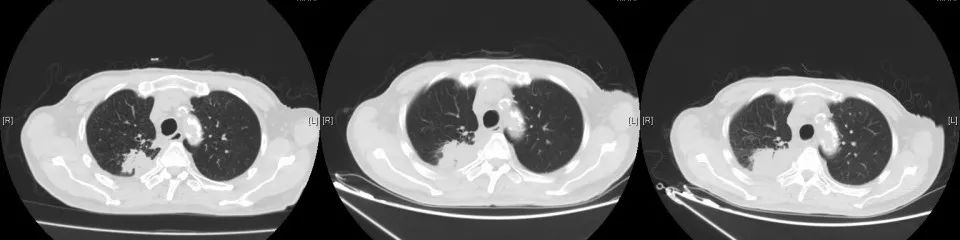

2021年5月19日常规复查CT考虑多发肝转移,肺原局部病灶稍进展。考虑吡咯替尼耐药,即予停用。即予“替雷利珠”200mg行免疫治疗1次。无明显副反应。2021年6月因肺部感染、合并心衰去世。

CT变化: